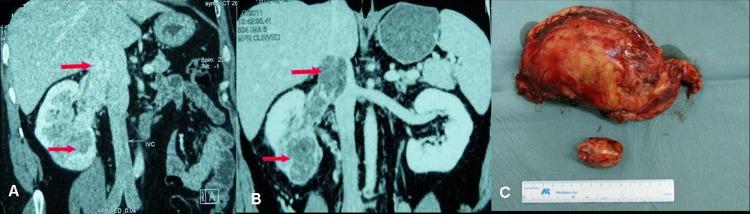

Among the 18 patients there were 13 male and 5 female, with a median age of 54.6 years. The objective response rate (ORR) of the operation on the selected patients is very high (94.4%), including 4 cases (22.2%) of partial response (PR) and 13 cases (72.2%) of stable disease (SD). After preoperative sorafenib treatment, the average tumor size of the 18 patients decreased from 7.8 cm (ranging from 3.6 to 19.2 cm) to 6.2 cm (ranging from 2.4 to 16.8 cm), and the median value of average tumor CT value decreased from 61HU to 52 HU. Among the 5 patients who had IVC tumor thrombi, the grades of tumor thrombi in 2 patients who were grade II before sorafenib treatment became grade I and grade 0 respectively, 2 patients of grade III both became grade II.

Preoperative neoadjuvant therapy with sorafenib for high risk RCC patients can significantly decrease primary tumor volume as well as tumor thrombus, which could help the nephron-sparing surgery (NSS) or radical nephrectomy to be done successfully.